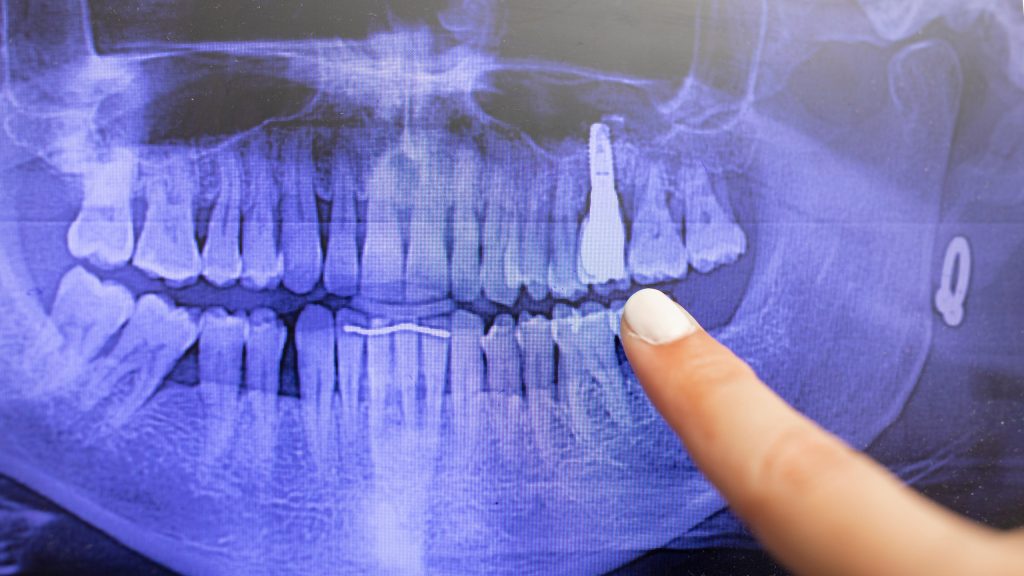

Identificación humana mediante implantes dentales

La identificación humana mediante implantes dentales en odontología forense es una de las estrategias más precisas y confiables dentro de las ciencias forenses contemporáneas; debido a la evolución que éstas ha experimentado en los últimos años al incorporar tecnologías biomédicas que permiten establecer identidades; incluso, en contextos donde métodos tradicionales resultan ineficaces. Cuando los tejidos […]